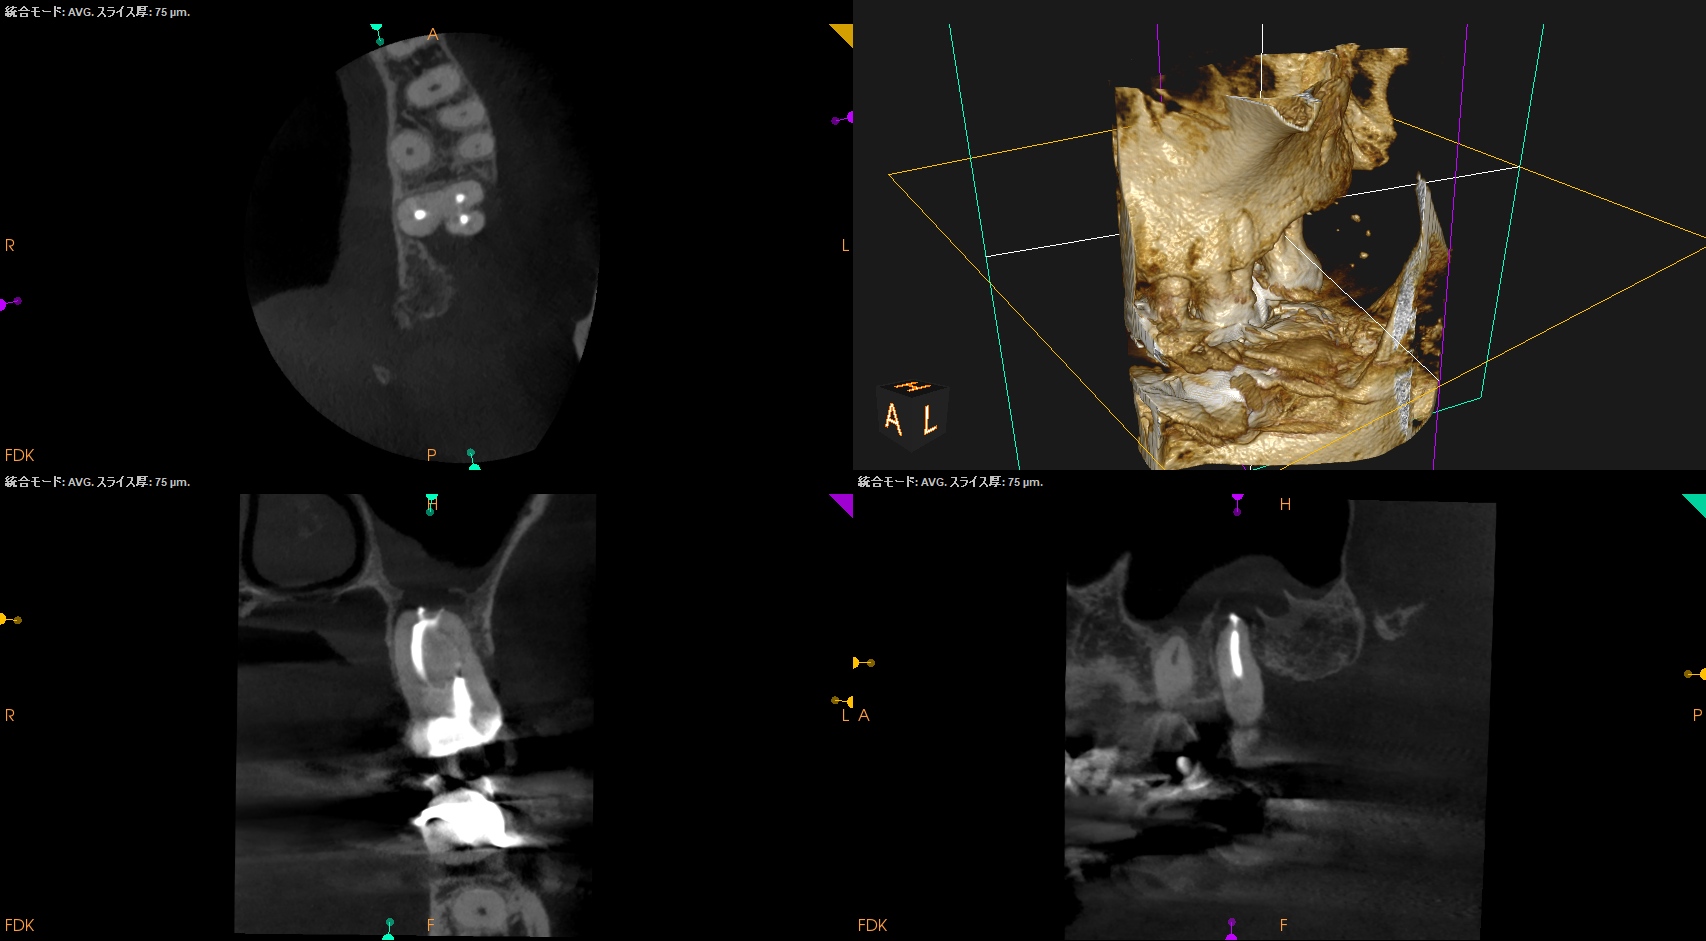

CBCT(2024.7.31)

MB

DB

P

根尖病変があり、上顎洞炎を呈している。

根管治療が必要だ。